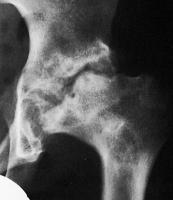

Hüftgelenk

Abbildung 7: Frühstadium mit beginnendem Kondensationsstadium links. Sowohl auf der ap-, als auch auf der axialen Aufnahme ist die angedeutete Verminderung der Höhe der Kopfkalotte mit leichter Verdichtung der Strukturen erkennbar.